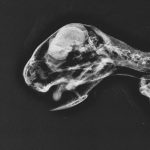

Foi realizado um enxerto heterólogo, que consiste no transplante de um indivíduo de uma espécie para outra. “Nós já havíamos realizado pequenas cirurgias de reparo em casco de jaboti, mas o procedimento na arara foi mais complexo. Utilizamos um bico de animal já falecido, que foi recortado, ajustado com resina de dentista e fixado com parafusos ortopédicos, de forma que a arara fique bem e consiga se alimentar”, acrescentou Cazati.

O procedimento cirúrgico durou 1h30, até a colocação, e envolveu uma equipe multidisciplinar do CRAS, com os médicos veterinários Lucas Cazati (cirurgião), Aline Duarte, Diogo Borges e Heitor Corrêa Lopes, além dos biólogos Allyson favero e Márcia Delmondes e a zootecnista Claudia Medina. “Importante ressaltar a parceria com a FAMEZ, da UFMS. O Setor de radiologia veterinária nos atende sempre que necessitamos com os exames de imagem”, lembra Lucas.